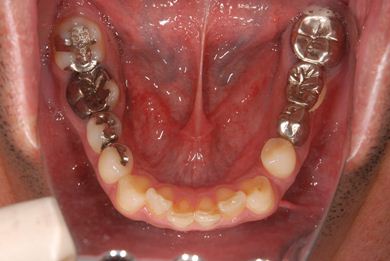

抜歯即日スピードインプラント治療

| 性別/年齢 | 男性 / 36歳 | ||||||||||||||||||||||||||||||||

| 主訴 | 前歯が折れていてないので、インプラント治療を希望。 | ||||||||||||||||||||||||||||||||

| 治療内容 | インプラント1本(抜歯即日スピードインプラント)、ハイブリッドセラミッククラウン1本 | ||||||||||||||||||||||||||||||||

| 総治療費 | 257,250円 | ||||||||||||||||||||||||||||||||

| 治療期間 | 7ヶ月 |